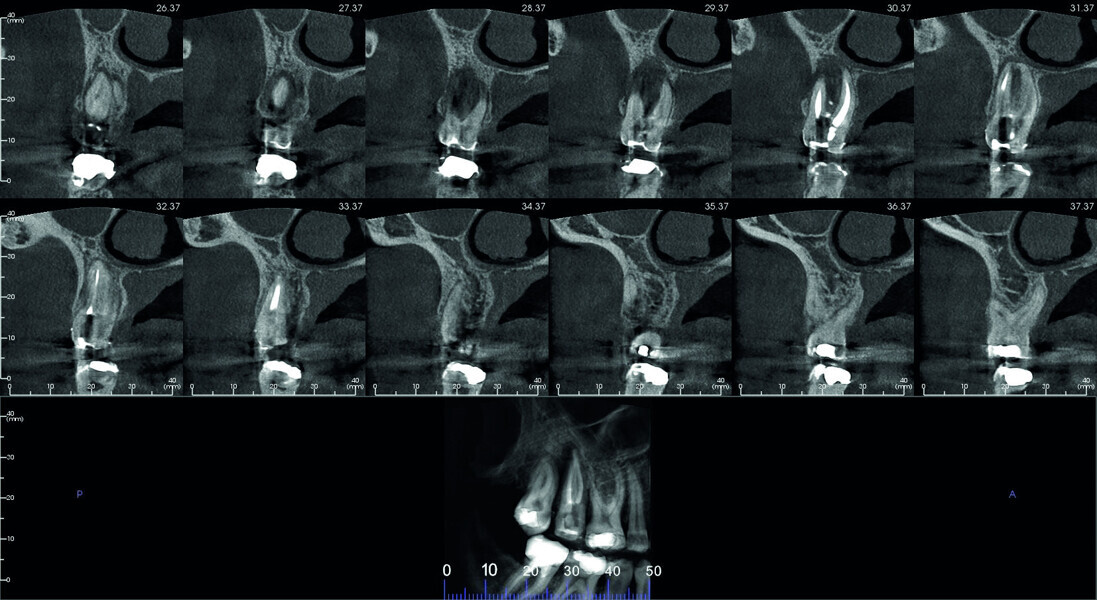

Fig. 4: Pre-op CBCT scan, pseudo-panoramic view.

Fig. 5: Pre-op CBCT scan, sections.

Fig. 6: Pre-op CBCT scan, detailed section of the maxillary second molar.

Fig. 7: Pre-op CBCT scan, coronal and sagittal views.